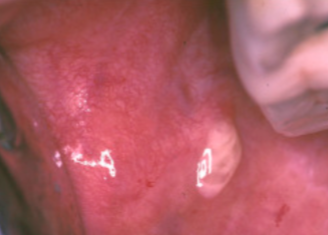

nicotine stomatitis

pipe and cigar contact

NOT precancer

inflamed salivary glands = volcano like papules with red central dots

nicotine stomatitis image